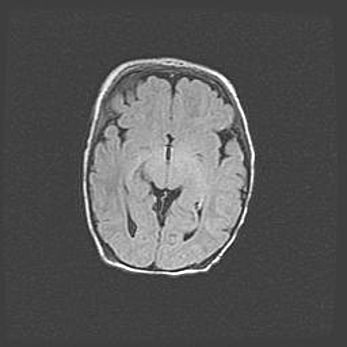

Неполная лизэнцефалия (пахигирия). Открытая гидроцефалия.

Возраст: 17 дней

Вес: 3110 г

Пол: мужской

Окружность головы: 33,5 см

Срок гестации: 35-36 недель

Лизэнцефалия—недоразвитие корковой пластинки и мозговых извилин в результате нарушения миграции нейронов коры. Поверхность мозговых полушарий гладкая. Микроскопически выявляется отсутствие нормальных слоев коры и скопление групп нейронов в подкорковом белом веществе.

Пахигирия—уменьшение числа вторичных извилин. В пораженном полушарии нервные клетки образуют толстый недифференцированный слой с неправильно расположенными нервными волокнами и группами гетеротопных клеток. Нервные клетки незрелые. Белое вещество истончено. При этом нередко аномально развит корково-спинномозговой путь.